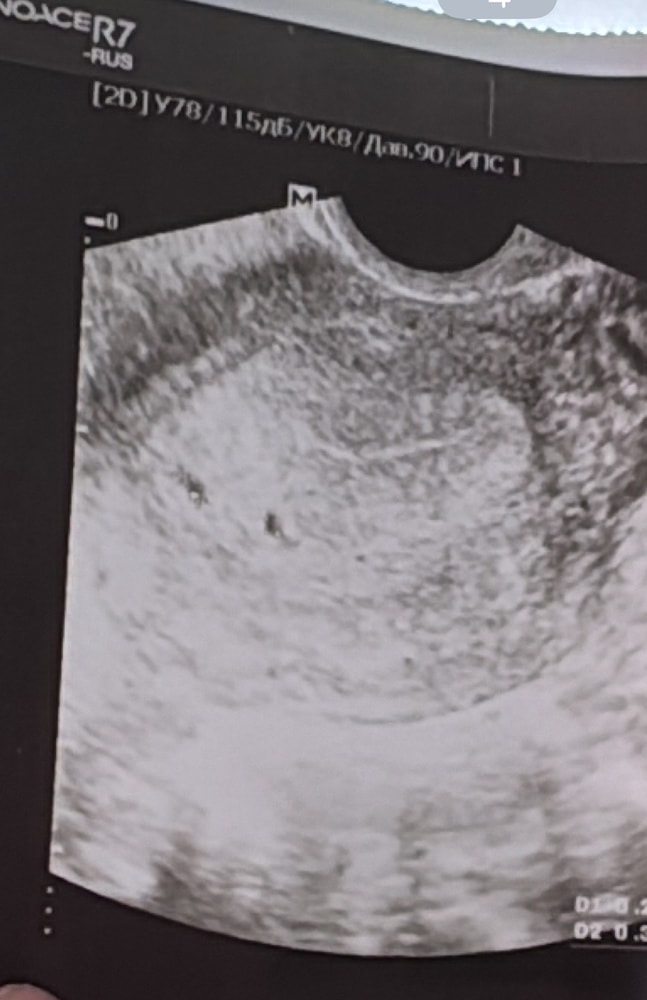

УЗИ, КТГ, доплерДобрый день! У кого было такое на первом узи сказали что двойня, через 3 дня сделала узи так как были боли низ живота там мне сказали что одно ПЯ?

1 узи